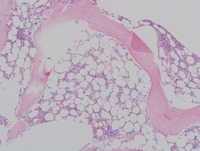

Bone Marrow

The bone marrow shows a hypocellular

marrow for age with atypical megakaryocytes and no increase in blasts. Cytogenetic analysis of the marrow showed an abnormal karyotype involving  monosomy 7.  DNA sequencing revealed a germline mutation in GATA2. Diagnosis:  Refractory cytopenia of childhood, GATA2 deficiency related.